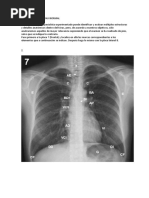

Radiografia de torax

• Toncidad de la caja torácica

Silueta cardíaca normal

• Contorno mediastínico derecho

• Contorno mediastínico izquierdo.

3: ventrículo derecho

• Cuando se está viendo en PA no se puede ver el

ventrículo derecho si no que se está viendo la

aurícula derecha.

1: Vena cava superior

4: Ventrículo izquierdo

2: Aurícula izquierda

Morado: tronco de la arteria pulmonar.